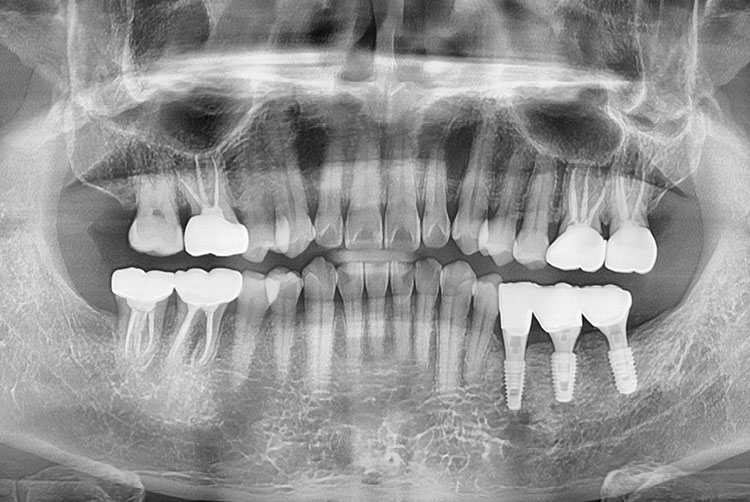

[임플란트] 임플란트

3797aa231884c139d12fb8ed2022c053.jpg

치료전 : 2016-02-20